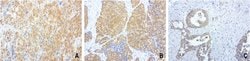

| Applications | Immunocytochemistry, Immunofluorescence, Immunohistochemistry (Paraffin) |